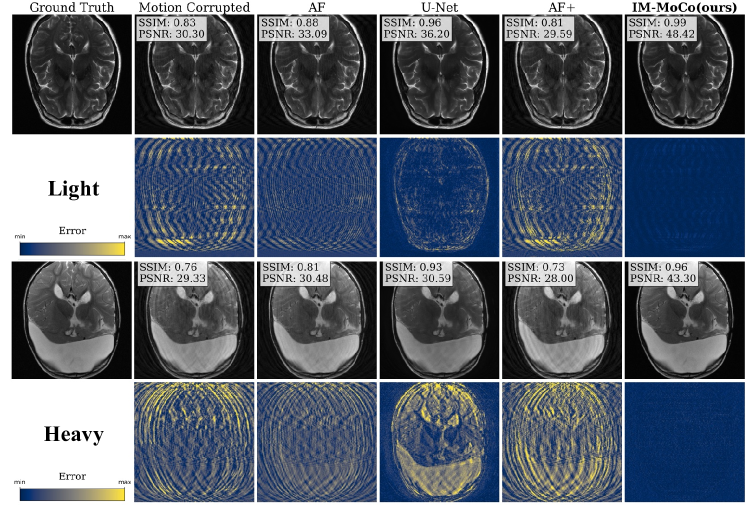

Experiment I: Motion Correction in Simulated Data. Table 1 shows quantitative results from the motion correction experiment. For light and heavy motion, corrupted images yield SSIM values of 87%percent8787\% and 74%percent7474\%, PSNR values of 28db28𝑑𝑏28\>db and 24db24𝑑𝑏24\>db, and HaarPSI values of 70%percent7070\% and 56%percent5656\%, respectively. AF and U-Net improve SSIM by 7%percent77\% and 10%percent1010\%, PSNR by 5db5𝑑𝑏5\>db and 3db3𝑑𝑏3\>db, and HaarPSI by 18%percent1818\% and 16%percent1616\%, respectively. However, AF+ worsens results by ca. 2%percent22\% across all metrics. Compared to the best baseline, AF, our method improves SSIM/HaarPSI by >4%absentpercent4>4\% for SSIM, >9%absentpercent9>9\% for HaarPSI, and >10dbabsent10𝑑𝑏>10\>db for PSNR. A qualitative comparison is shown in Fig. 2.

Refer to caption

Figure 2: The visualization shows the median results of motion-corrected images of our IM-MoCo pipeline besides motion-corrupted, ground truth, and comparison methods. The first and third rows show the light and heavy correction results, respectively. The second and fourth rows show the residual error images.

Experiment I demonstrated that our method effectively enhanced the quality of motion-corrupted images, surpassing comparison methods, which is mainly contributed by the implicit image priors and DC with the acquired k𝑘k-space in the forward motion model. Notably, our approach exhibited robustness in addressing heavier motion scenarios as evidenced in Fig. 2 and Table 1. However, the efficacy of our method hinges on the accurate detection of the k𝑘klD-Net, which is contingent upon the acquisition sequence and motion simulation pattern. In Experiment II, we showcased the performance enhancement of a classification task compared to both corrupted and U-Net-corrected images as indicated in Table 2. This improvement in classification accuracy can be attributed to the prevention of overfitting on "healthy" features in instance-optimization methods in contrast to population training ones like the U-Net. Although our work primarily revolved around 2D rigid motion, we are confident in the method’s potential for extension to more complex motion and multi-coil data. This can be achieved by incorporating coil sensitivity map estimation following the third step of the pipeline. Future investigations will explore the utilization of different sampling patterns, such as radial sampling, and the adaptation of the motion detection network to these patterns or pattern-independent methods. While real motion cases were not tested in this study, we are optimistic regarding the adaptability of our method through adjustments to the motion detection network.